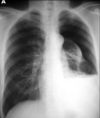

A

Consolidación alveolar

How well did you know this?